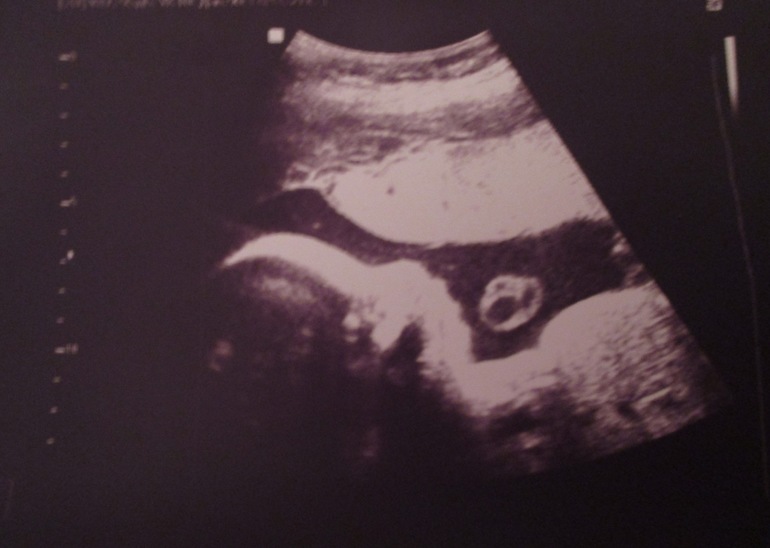

Вот и прошли мы последнее УЗИ)))

УЗИ, КТГ, доплерМасечку мне не показали, только фото распечатали. Всё с малышом хорошо, весим уже

1 кг 660 г. Не маловато ли?

Он так буянил когда датчиком водили по животу. Не понравилось ему))))

Ну и окончательно подтвердили сыночка! Теперь у нас будет и доча и сын! Как здорово!

Ну и наше фото: пузырей понапускал)))))